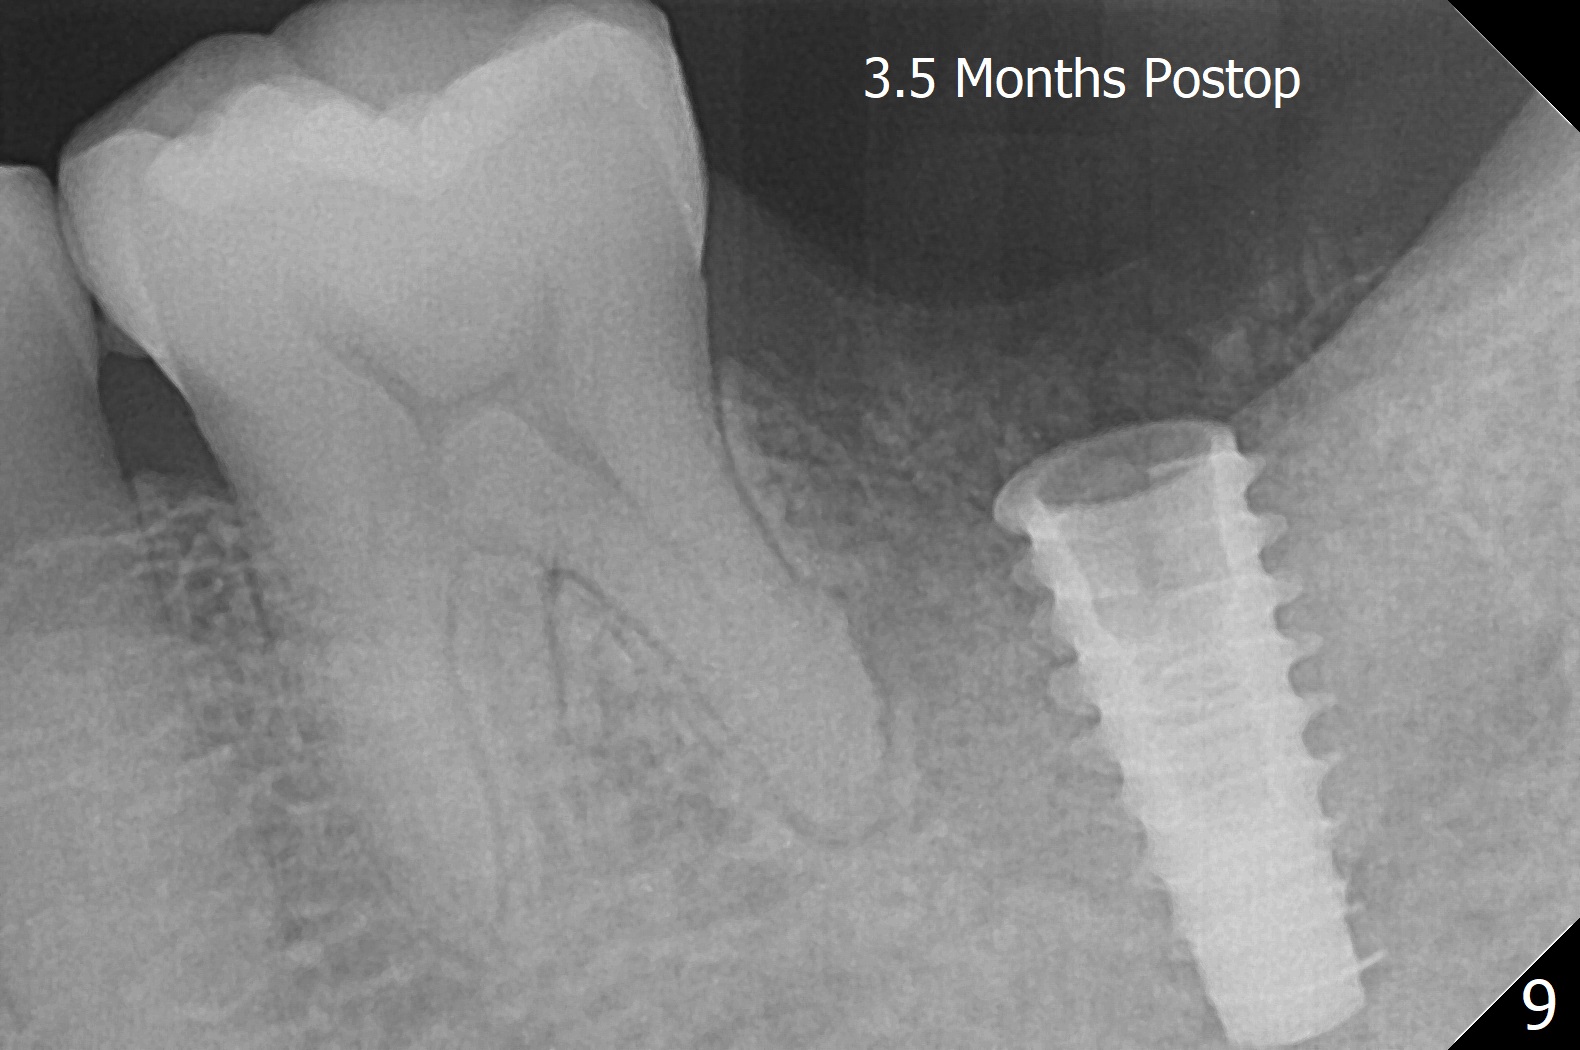

After placement of a 5x11 mm implant and cover screw at #18, allograft mixed with PRF (sticky bone) is placed in the peri-implant space, but it appears that bone density in the apical region (Fig.1 A) is lower than that in the coronal one (C) because of a constriction between the implant and the distal crest (*). Ideally the undercuts (Fig.2 *) of the extraction socket (black area) should be identified. Place bone graft in the undercuts (Fig.3 red circles) after osteotomy (white outlines) and before implant placement! A 4.5x1 mm temporary abutment is placed for an immediate provisional. The 2nd shortcoming of this case is that the implant is placed a little buccal. The papilla mesial to the immediate provisional (Fig.4 P) looks normal 4 days postop (no food impaction is expected when a final restoration is cemented). Additional acrylic (*) was placed to close a buccal gap when the provisional was seated with the temporary abutment. The patient reports loss of a piece of material in 4 days. It must be the additional acrylic, since it is absent 6 weeks postop (Fig.5). The provisional (Fig.5 P) looks wide, probably related to post-extraction gingiva and bone atrophy (Fig.6, 7 *). Bone graft (Fig.6 <) becomes a component of the gingival cuff. The provisional is re-trimmed for better oral hygiene. The gingival cuff is basically healthy 3.5 months postop, although the temporary abutment is loose and the implant is tender to rewinding and winding (Fig.8). The implant seems to remain non-osteointegrated 3.5 months postop (Fig.9). Although the bone density around the implant increases nearly 6 months postop (Fig.10), the implant remains tender when a 5x4(4) mm pair abutment is tightened. The healing abutment is reused. The bone density around the implant increases 11 months postop (Fig.11). Uncover is done with 5.5 mm profile drill. One month post uncover (12 months postop), the implant remains unstable (Fig.12). Prepare sticky bone x1. Make incision for exploration, including retightening the implant after Titanium brush and H2O2 Q-tip rubbing. If needed, a larger and shorter UF implant is a replacement (Fig.13). The implant is removed, cleaned with Titanium brushes and H2O2 in vitro and repositioned 12 months postop (Fig.14: arrow (gaps: post granulation tissue removal)). The gaps are regrafted with sticky bone and covered with PRF membrane and Cytoplast. Although the patient complains of severe pain the first 2-3 postop, the wound is apparently healing 12 days postop. The Cytoplast is exposed asymptomatic 5 weeks postop (Fig.16) and removed (Fig.17). The wound appears to have healed without loss of the bone graft (Fig.18).术后四个月伤口愈合,骨粉几乎没有丢失,有骨小梁形态(图十九:*)。切开,刮匙去骨,有一定硬度,即刻放置修复基台,完全就位(图二十),制备临时牙冠,牙周敷料固定组织瓣(没有缝线)。